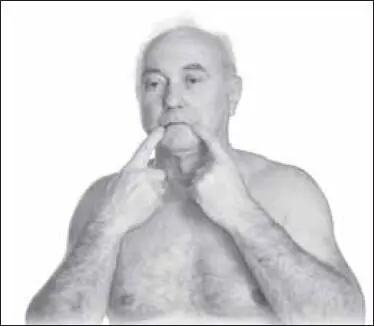

Далее массируют точки ди-цан (находятся по уголкам рта) (рис. 136).

Массируют одновременно обе симметрично расположенные точки. Воздействие короткое, быстрое, с усилием 2–3 кг (до 10–20 секунд). Этот вариант точечного массажа можно при необходимости повторять.